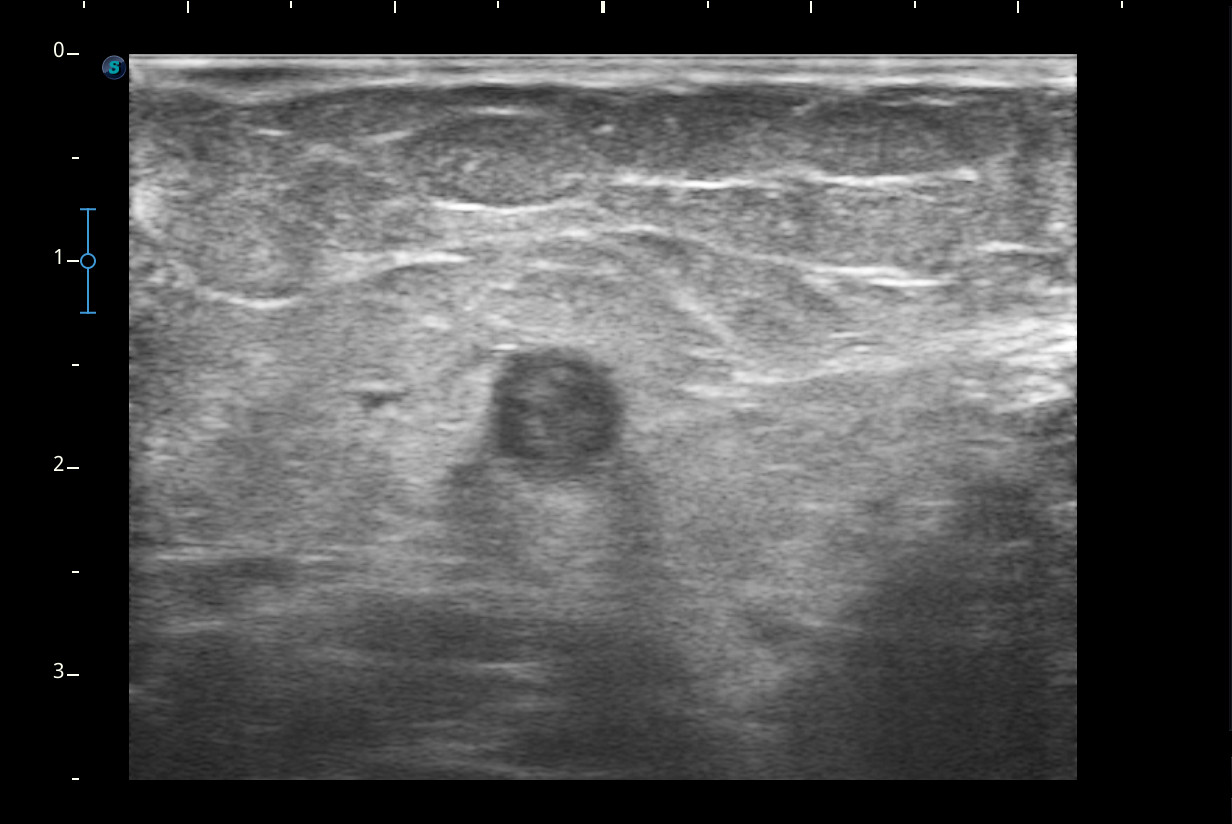

Hallazgos ecográficos

Se visualiza congestión del tejido subcutáneo del brazo y ocupación de la luz de la vena basílica del brazo por un trombo.

Diagnóstico: trombosis venosa de la vena basílica del brazo derecho. Concordancia con el hospital en el segundo tiempo que acude la paciente.